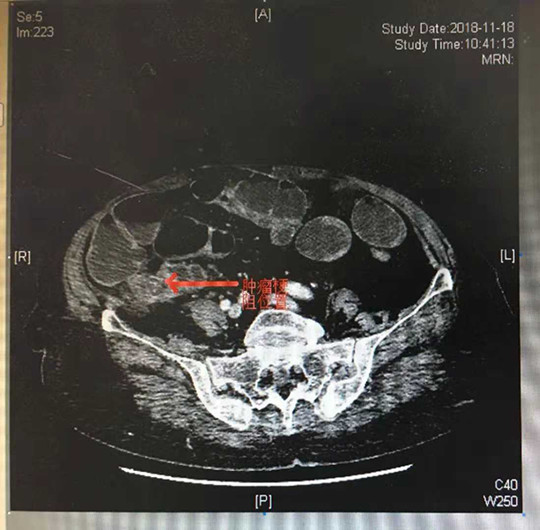

20多天前,赵老太开始出现大便不通、腹痛、腹胀。在当地医院治疗10多天,症状持续加重。家人带老人到我院就诊。11月20日下午3时入住我院普外科二病区。入院后,老人出现阵发性腹痛,频繁呕吐等症状,普外二病区徐本文主任根据老人状况初步诊断为机械性肠梗阻,于是立即进行相关检查,腹部增强CT显示小肠广泛扩张,考虑回盲部肿瘤引起梗阻。这种疾病保守治疗是无效的,如果不尽快手术,老太将有生命危险。但是手术的话,风险非常大,因老太太年龄太大,要做的是高难度手术,麻 醉就存在很大风险。尽管难度大、风险高,但冒险做手术至少还能让老人有活下去的希望。

徐本文主任对老人的病情非常重视,立即请示周业庭院长。周院长闻听后亲自到病房查看患者,并组织****科汪涛主任及多学科进行会诊,积极讨论,大家认为老人虽然年纪大,手术风险高,但只要准备充分,精细操作,手术的成功率还是比较高的,为了老人的生命,冒险也是值得的。遂研究制定了详细周密的手术方案,并与老人家属充分沟通,得到了家属的积极支持和配合。随后,周业庭院长和徐本文主任给赵老太太行急诊手术,术中发现肿瘤位于盲肠,肠管完全堵塞,并侵犯右侧腰大肌及后腹膜,小肠广泛扩张,立即行根治性右半结肠切除术。术中出血较少,手术取得圆满成功。